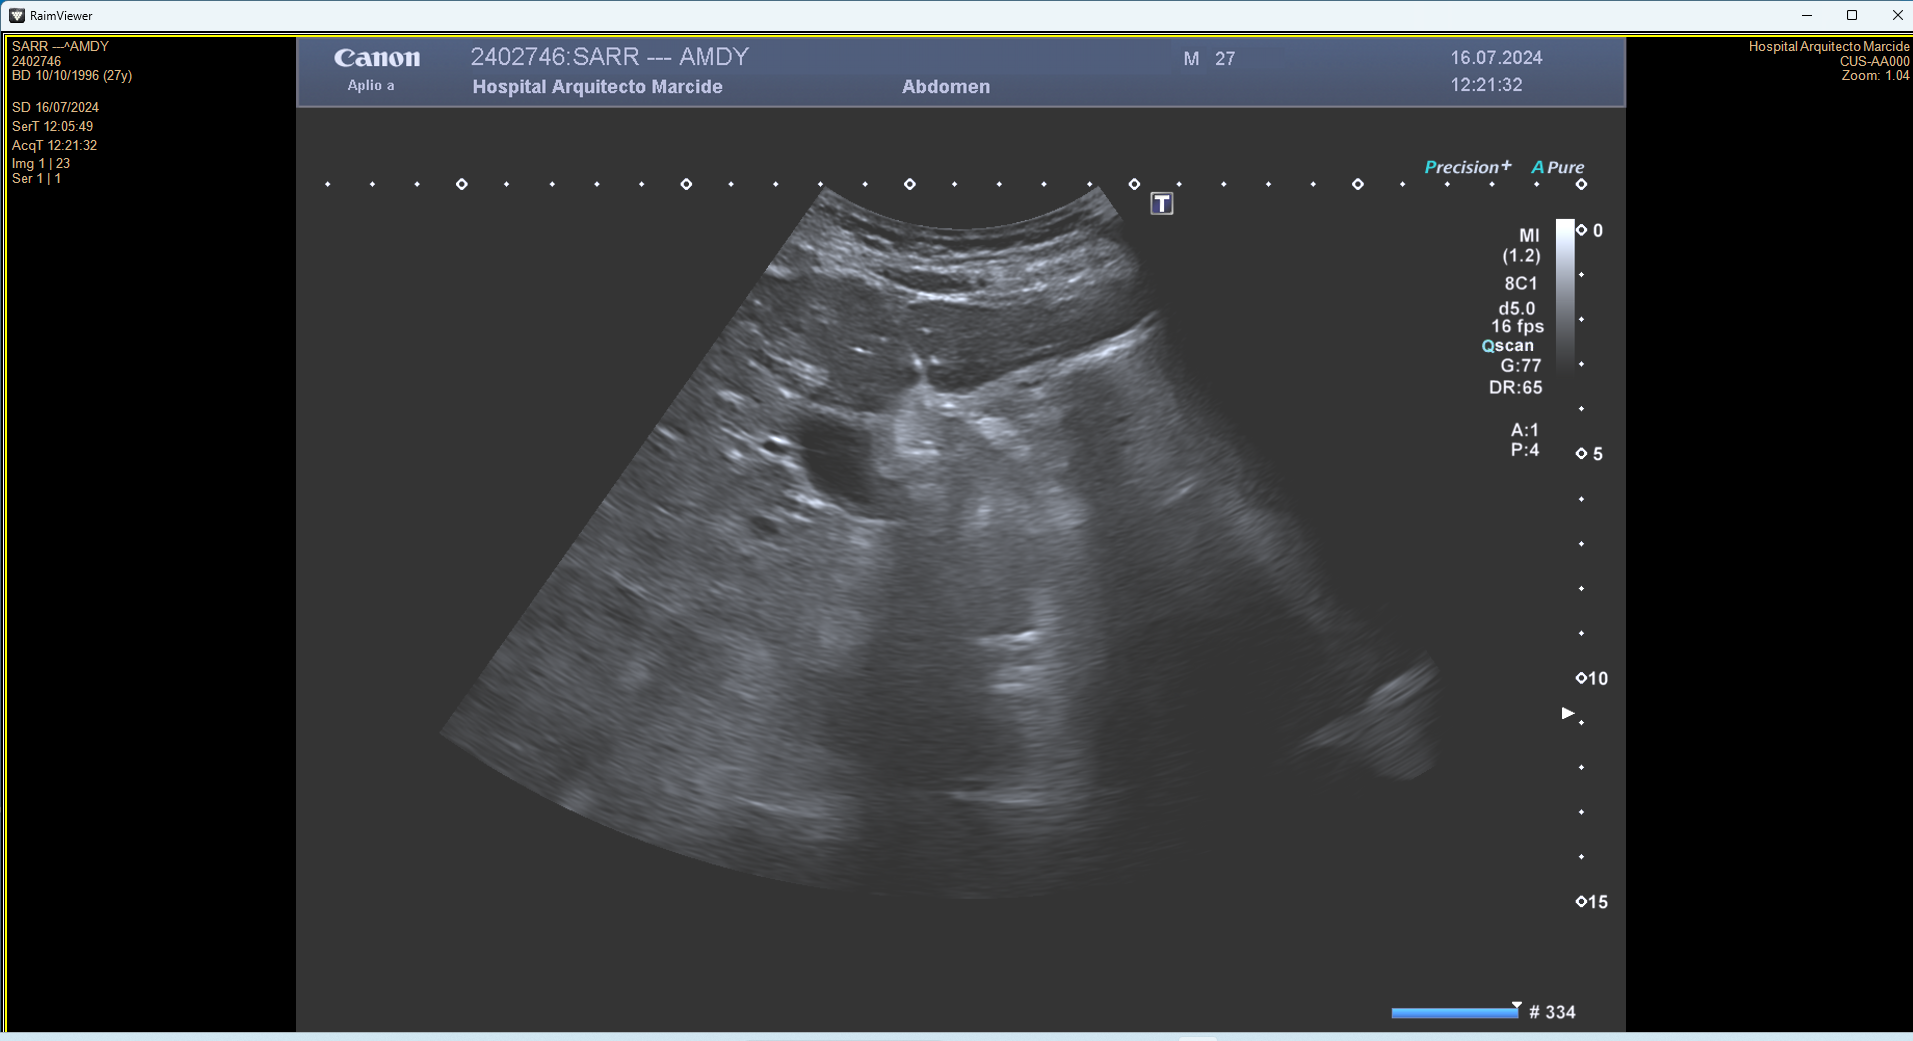

En ecografía en Centro de Salud: La práctica totalidad del parénquima hepático se encuentra sustituida por múltiples lesiones sólidas nodulares hiperecoicas, de predominio en el lóbulo hepático derecho, donde presentan tendencia a la confluencia y conforman una masa que alcanza los 13 cm de diámetro máximo. La vena porta es permeable y ectásica, con esplenomegalia. Ambos son signos de hipertensión portal.